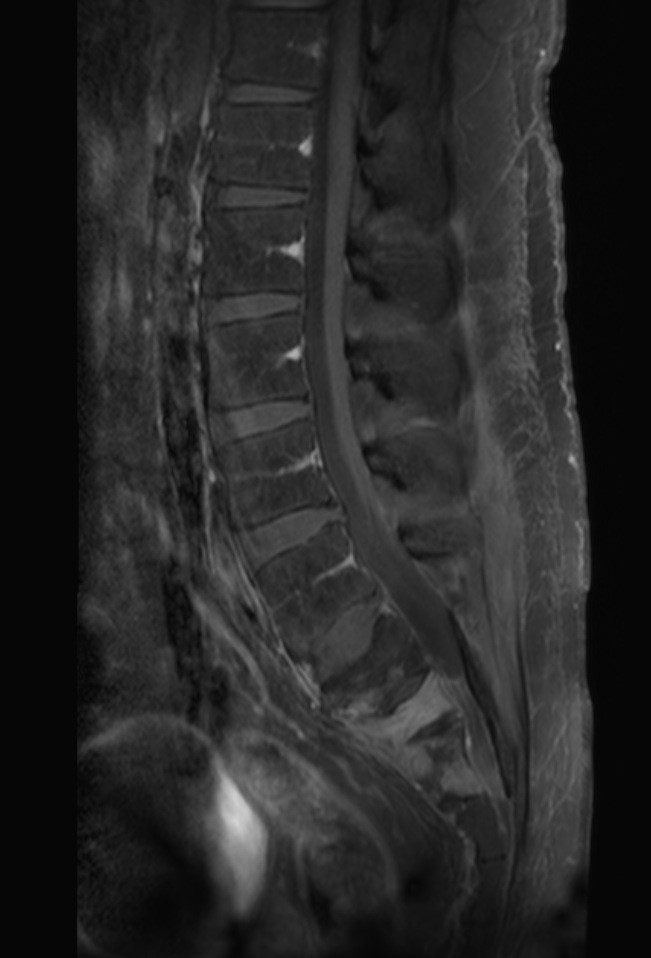

Primary lymphoma of the sacral bone is a rare myeloproliferative disease, occurring mostly after 4th decade of life and mainly in male patients. We reported a case of sacral bone lymphoma in a 24-year-old man with low back pain and radiculopathy. Imaging showed a sacral bone lesion which later proved to be non-Hodgkin’s lymphoma on histopathologic study. Lymphoma of the sacral bone is chemoresponsive and carries a good prognosis. Sacral bone lymphoma should be considered as a differential diagnosis in patients with low back pain who is not responding to analgesic treatment.